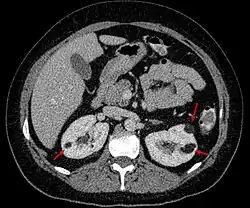

Angiomyolipoma in both kidneys (arrows) in computer tomography. The tumours are hypodense (dark) due to fat content. | |